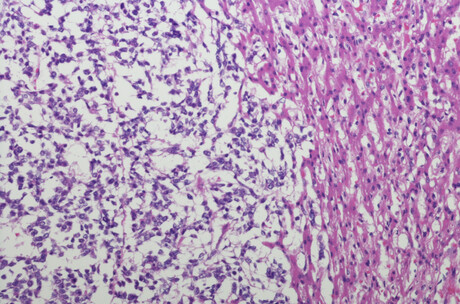

The researchers created three models; they implanted into mice tumour tissue that was either taken from patients, or from two cancer cell lines called HepG2 and TT001 established from patients’ tumours and cultured in the laboratory. The tumours and cancer cells all had CTNNB1 mutations. The mice were treated with WNTinib and the effects were measured against untreated mice or untreated cells.

In the second model, in which mice were implanted with the HepG2 cell lines, WNTinib significantly delayed tumour growth compared to the control group. On day 8, treated tumours were 30% smaller than in the control group and 46.5% smaller on day 10. The median (average) survival for the treated mice was 16 days compared to nine days for the control group. The last mouse in the control group lived for 21 days, while (at the time of writing), one mouse in the treatment group was still alive after 148 days.

Similarly, in the model in mice implanted with TT001 cell lines, WNTinib significantly delayed tumour growth. On day 8, treated tumours were 26% smaller than in the control group and 23% smaller on day 10. These mice also survived for longer; 45% of them lived longer than 30 days and three mice were still alive after 106, 118 and 127 days, compared to the control arm where none survived beyond 20 days.

“Notably, tumours shrank in 45% of the TT001 animals treated with WNTinib and, of these, the tumours disappeared completely in 80% of them,” Balaseviciute said.